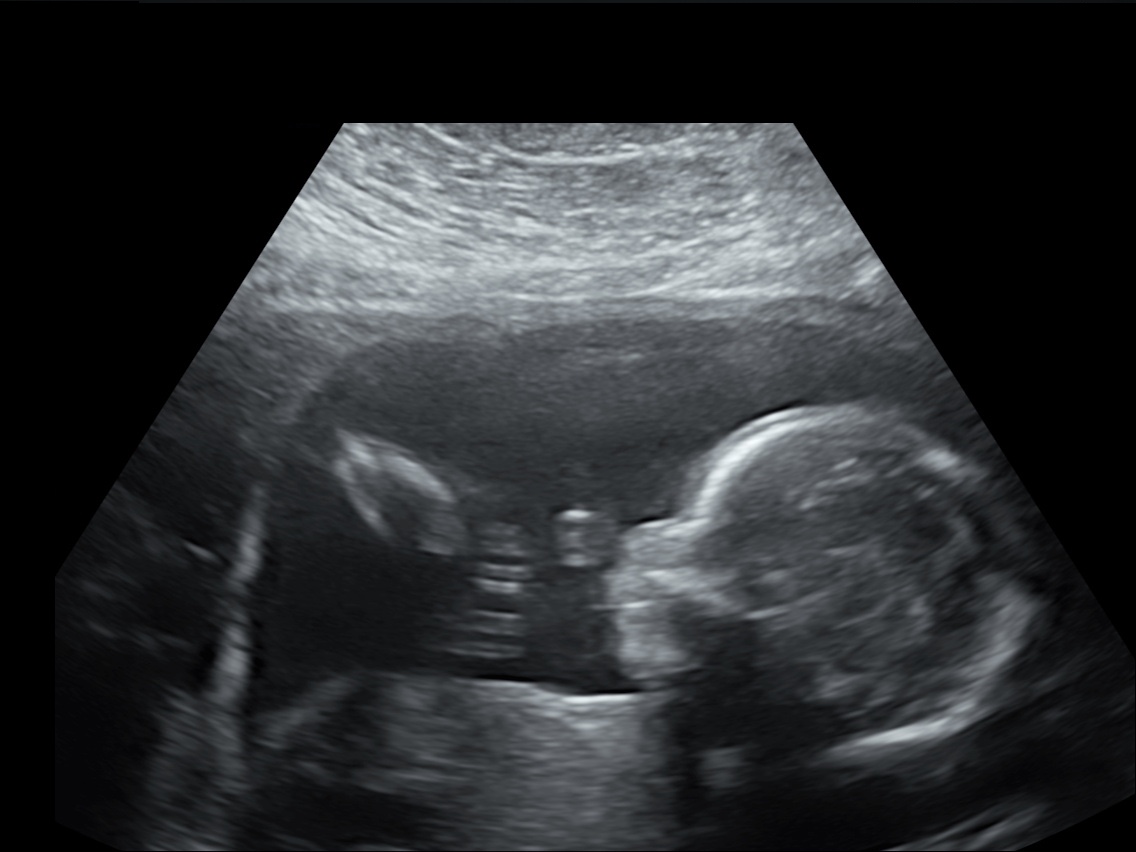

21 weken

Een echo na 21 weken.